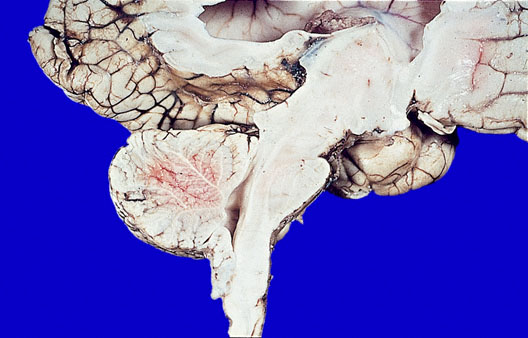

A female infant dies at the age of 2 months. She underwent closure of a lumbar myelomeningocele 24 hours after birth. A photograph of a sagittal section of the brain is shown. Which of the following is most likely present in this infant’s brain?